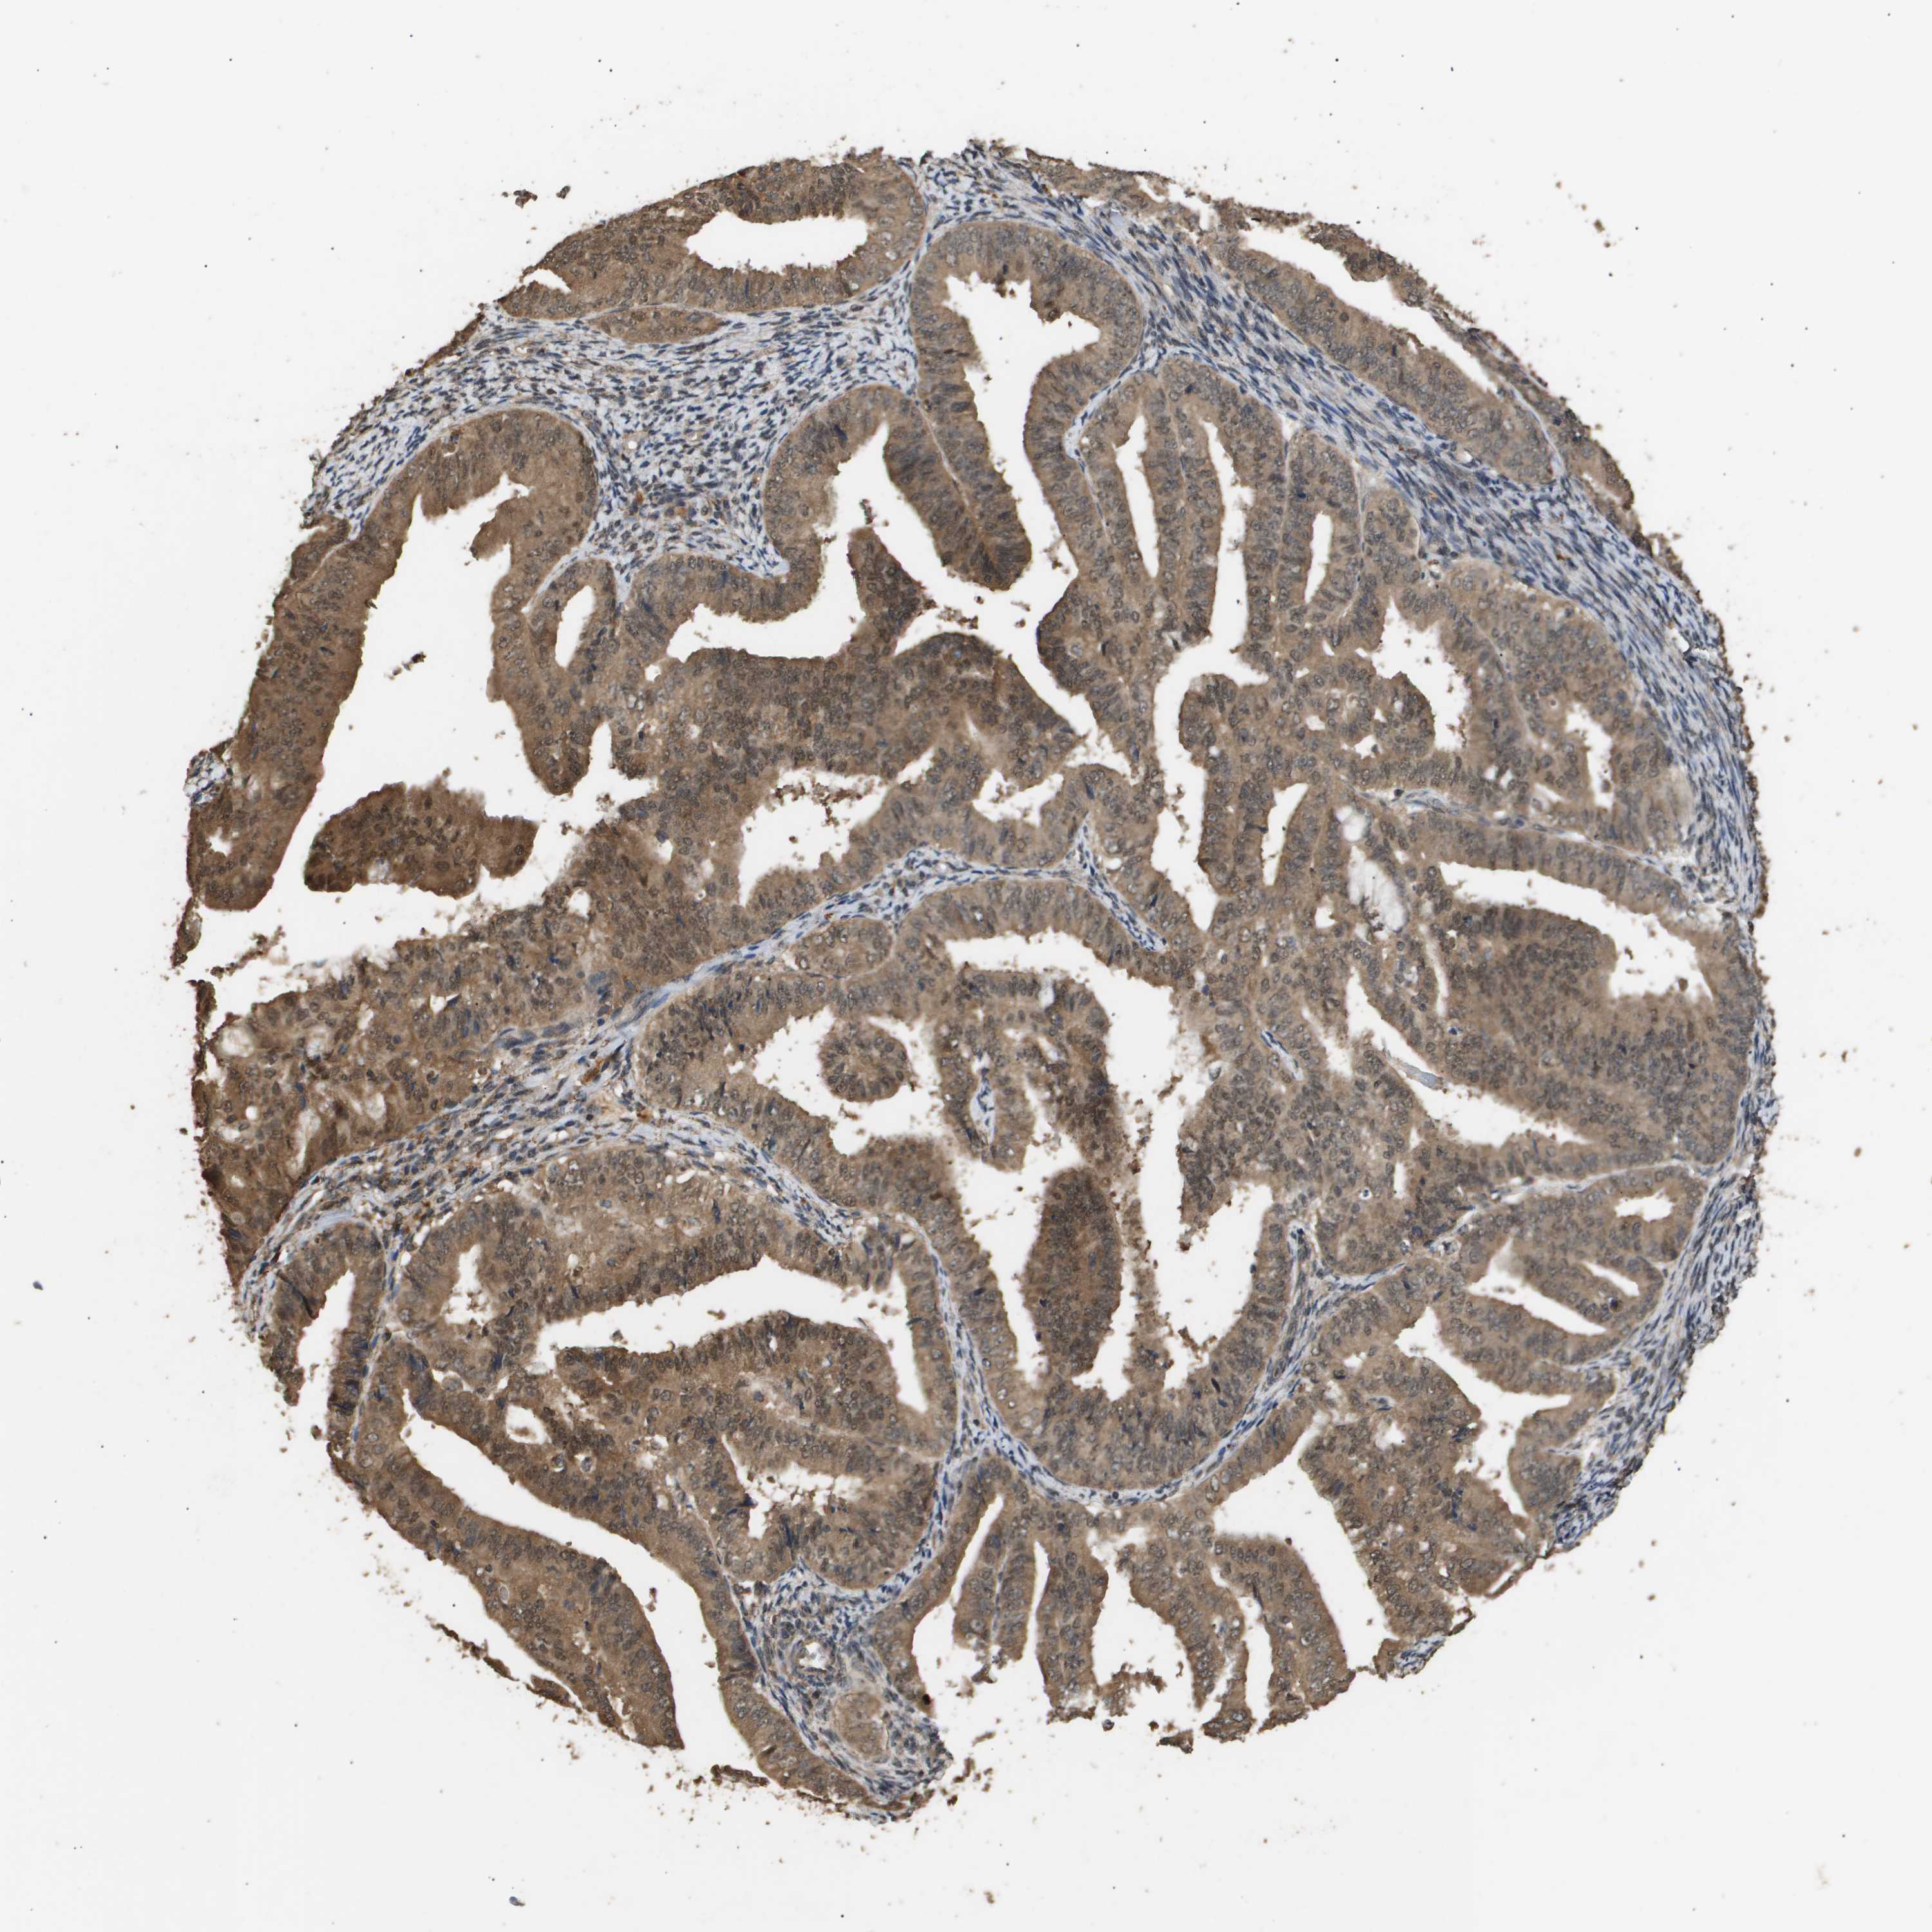

ENDOMETRIAL CANCER - Protein expressioni

A mouse-over function shows sample information and annotation data. Click on an image to view it in a full screen mode. Samples can be filtered based on level of antibody staining by selecting one or several of the following categories: high, medium, low and not detected. The assay and annotation is described here.

Note that samples used for immunohistochemistry by the Human Protein Atlas do not correspond to samples in the TCGA dataset.

Antibody stainingi

Antibody staining in the annotated cell types in the current human tissue is reported as not detected, low, medium, or high, based on conventional immunohistochemistry profiling in selected tissues. This score is based on the combination of the staining intensity and fraction of stained cells.

Each image is clickable and will lead to virtual microscopy that enables deeper exploration of all samples and also displays staining intensity scores, fraction scores and subcellular localization as well as patient and tissue information for each sample.

Antibody CAB016136

Antibody CAB017773

Staining

High

Medium

Low

Not detected

Intensity

Strong

Moderate

Weak

Negative

Quantity

>75%

75%-25%

<25%

None

Location

Nuclear

Cytoplasmic/membranous

Cytoplasmic/membranous,nuclear

Adenocarcinoma, NOS